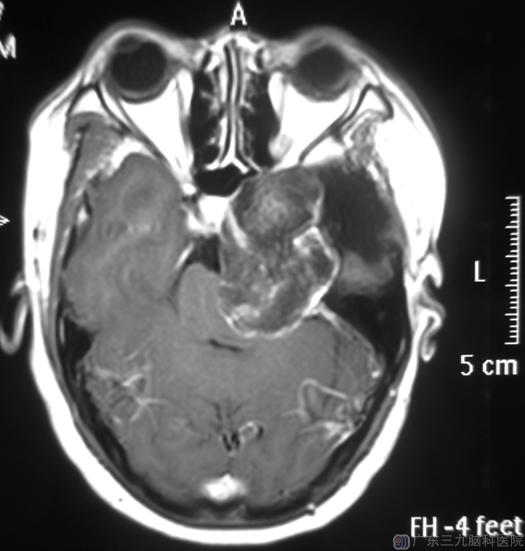

半年前,严姐的面部麻木以及眼部发作性抽搐等症状逐渐加重。去年10月在陪同表妹来广东三九脑科医院治疗的时候,听从医生的建议顺便复查了一下,结果显示:左侧中后颅窝占位性病变,考虑胆脂瘤复发,大小为:5.9cm×4.0cm×4.1cm。

今年3月份,严大姐入住广东三九脑科医院综合神经外科,查体:左侧额颞部可见一陈旧马蹄形切口;左侧眼球结膜稍充血,左侧眼球外向及向上运动障碍,粗侧左侧视野出现复视;左侧面部麻木,左侧面部肌肉较右侧萎缩,左侧咬肌肌力较对侧差。